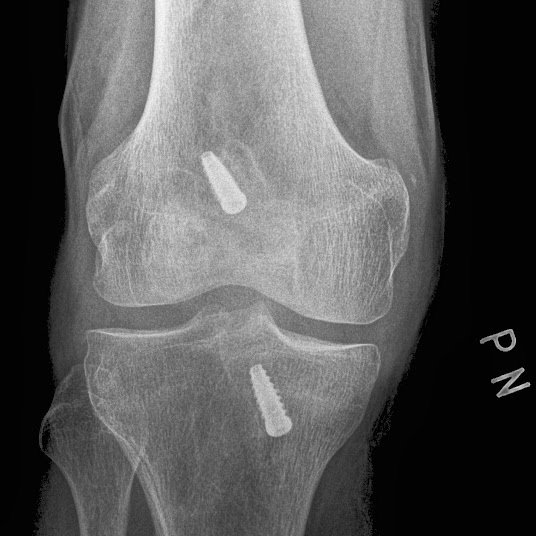

…a zase to koleno Od mikha-el - 29. 10. 2013 0 FacebookXPinterestWhatsAppLinkedinReddItEmailPrintTelegramCopy URL Najděte, kde je chyba (RTG z 21. 10. 2013)… SOUVISEJÍCÍ ČLÁNKYVÍCE OD AUTORA Blogy Mužská rezerva šestá v jednokolové baráži Blogy Birell Grand Prix Praha 10 km Blogy Tyden 30-31 Blogy Tréninkový deník: srpen 2017 Blogy Maga SkyMarathon Blogy #HVFsrpna